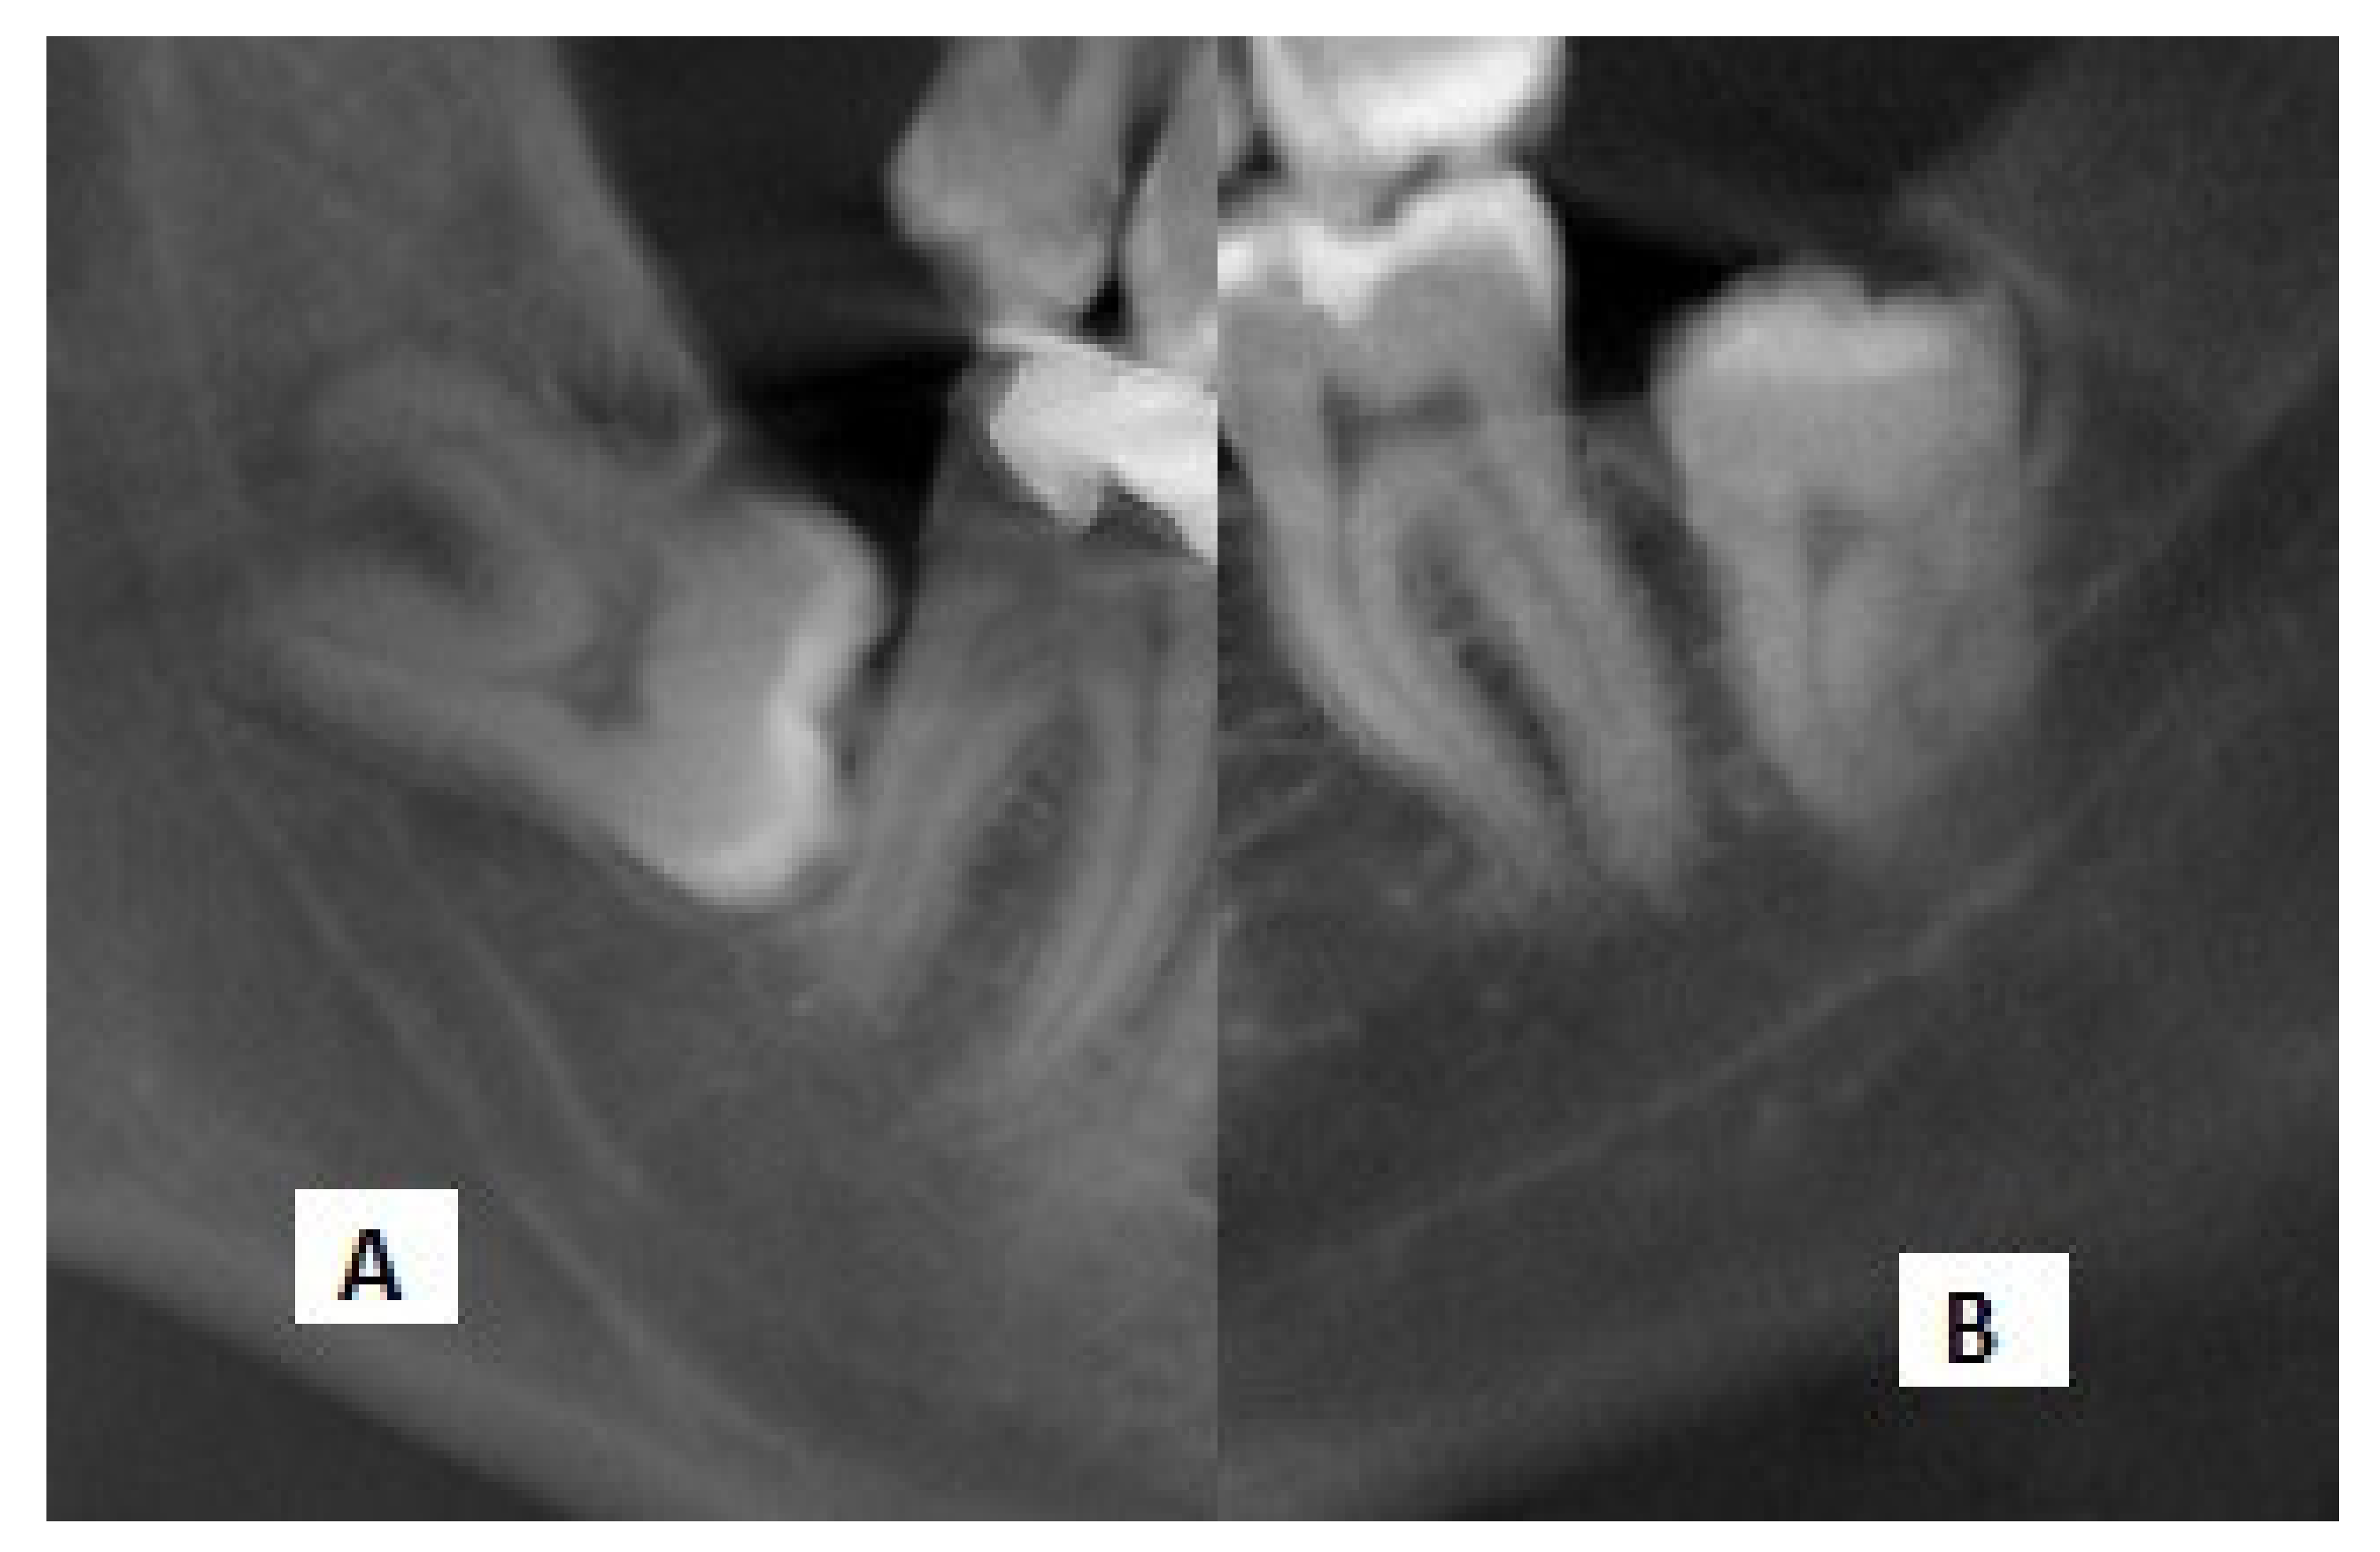

Figure 2.

Cropped panoramic radiographs showing the (A) interference with the white line and (B) darkening of roots.